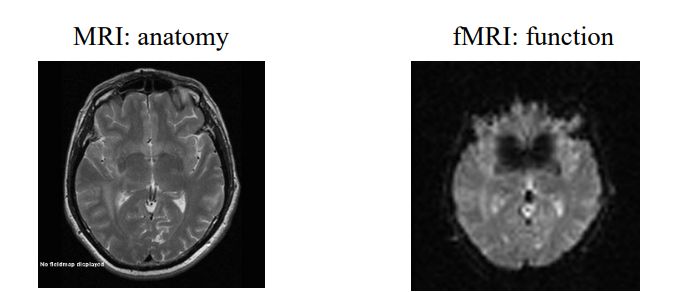

Name differences of fMRI and standard MRI.

MRI:

- anatomy

- high resolution (~1mm)

- beautiful

- slow (~100s)

fMRI:

- function

- low resolution (~4 mm)

- ugly

- fast (~0.1s)